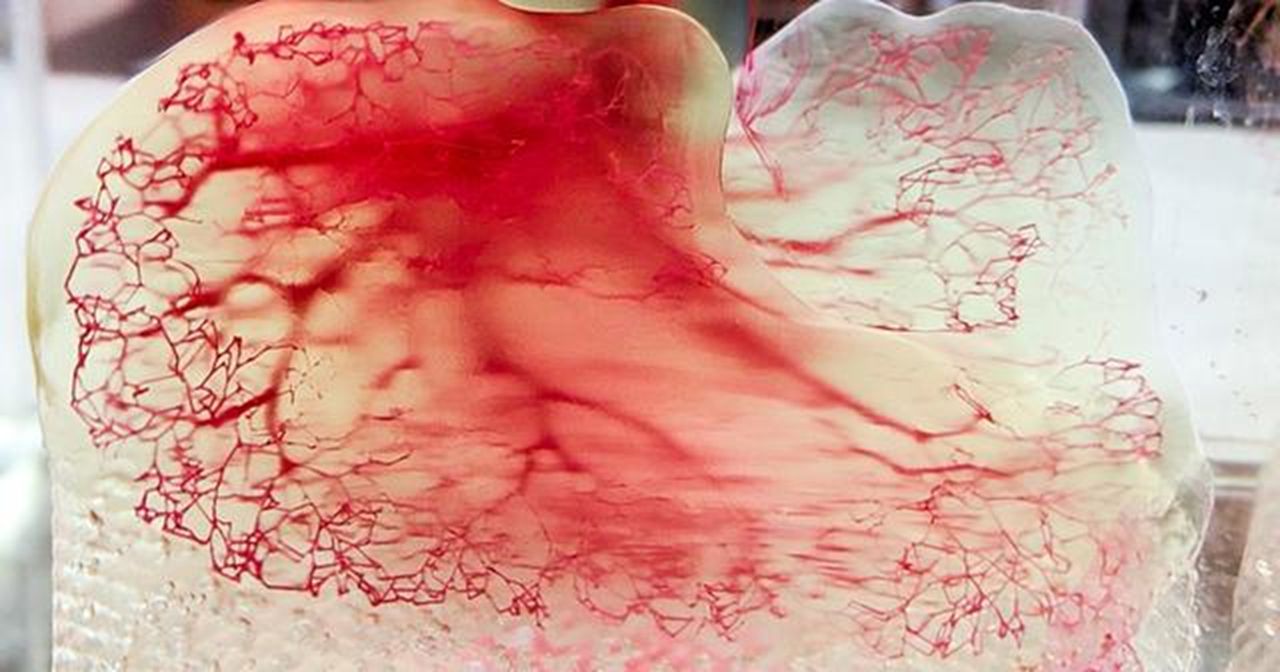

Readily3D Attempts Volumetric Human Organ Bioprinting

Readily3D, one of the first companies to tackle the new volumetric 3D printing process, has adapted their process for bioprinting.

TU/e Uses Xolography to 3D Print Living Cells

The research could lay the foundation for printing complex biological tissues, such as kidneys and muscles.